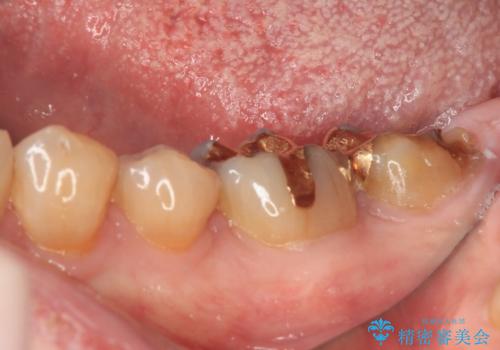

1番奥の歯はゴールドインレー周りがむし歯で欠けており、手前の歯はインレーの下にむし歯がある状態でした。

1番奥は歯肉に覆われている部分が大きいため、欠損部とむし歯の部分をゴールドインレーにて修復し、手前の歯はオールセラミッククラウンにて補綴治療を行うこととしました。